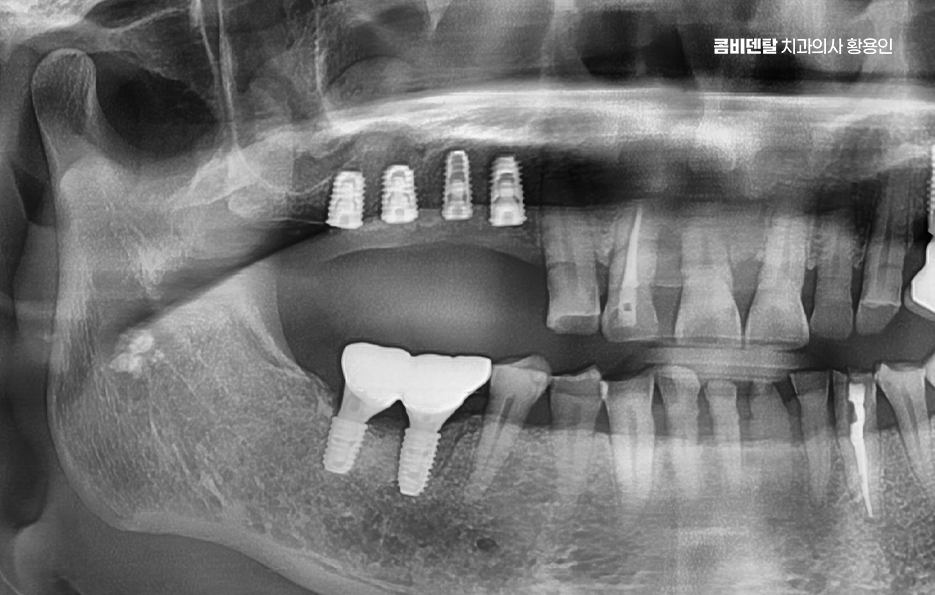

어금니 임플란트 과정은 정밀 진단에서 시작되며 잇몸뼈 안에 인공 치근을 심는 방식이기 때문에 뼈 상태 확인이 필수적으로 파노라마 촬영이나 3차원 CT를 통해 뼈 높이와 폭, 신경 위치를 확인하고 특히 아래 어금니는 하치조신경과 가까워서 정확한 위치 파악이 중요하며 위 어금니는 상악동과의 거리도 고려해야 할 필요가 있어요

임플란트를 심을 잇몸 뼈가 충분하다면 바로 식립이 가능하지만 치아를 빼고 오래 방치한 경우에는 뼈가 흡수되어 부족할 수 있으며 이때는 뼈이식을 먼저 하거나 동시에 진행하고 어금니는 씹는 힘이 강하기 때문에 초기 고정이 단단해야 하며 유지까지 고려할 때 교합의 정교한 맞물림이 중요한 부위라고 할 수 있었어요